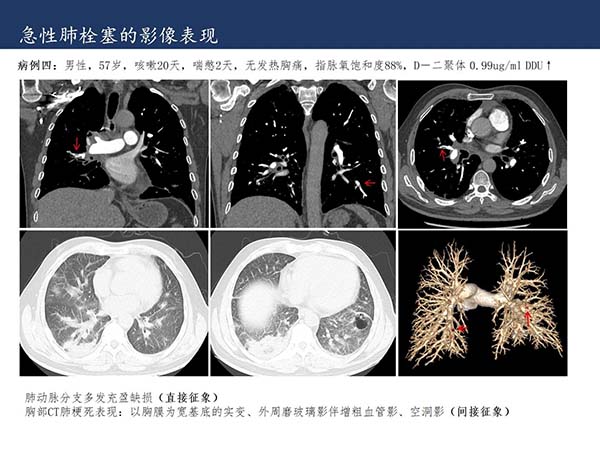

【杨柳病例】危急值病例:急性肺栓塞的影像表现